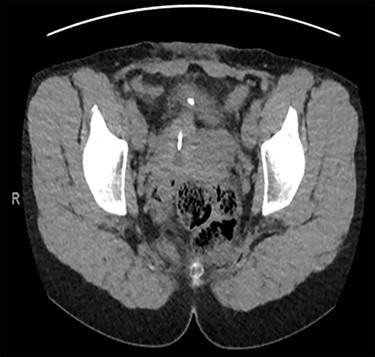

Computed tomography (CT) scan including a urographic phase revealed an IUCD in the vesico-uterine space, with one horn embedded into the bladder (Figs 2–4).

Sagittal CT urinary tract image demonstrating the device lying between uterus and bladder.